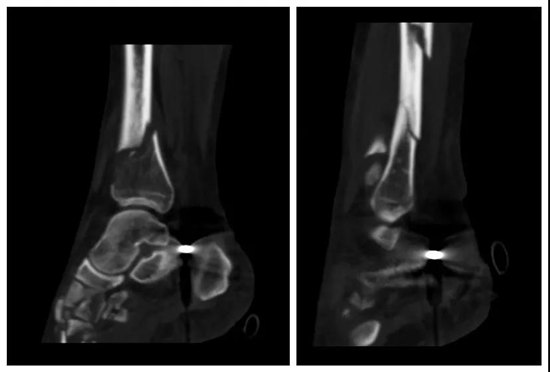

转入ICU后,经过气管插管、补液扩容、抗感染等积极治疗抢救后,何阿姨病情暂时稳定,但仍伴有持续发热、意识模糊等症状。骨伤一科毛勇主任等医师查房时发现患者脓毒血症明显。但感染灶从何而来呢?经过仔细查体发现患者右小腿骨折处皮肤伤口有一小指甲大小的黑痂皮,揭开痂皮见脓液渗出。打开外院缝合口后见,大量脓液持续流出,结合相关检查,毛勇主任等立即意识到这是一例非常罕见的坏死性筋膜炎。该病情极为凶险,若救治不及时随时有危及生命的可能;即使勉强保住生命,患肢也会坏死导致截肢,必须马上手术,进行切开排脓、彻底清创、抗感染抗休克等治疗。遂立即送何阿姨到手术室行清创+VSD(负压封闭)引流手术,术中见大量灰白色坏死组织,小腿筋膜大量坏死、水肿、血栓形成;并见大量淘米水样脓液,皮下组织坏死清创后骨折处外露,手术中冲洗伤口用掉了30000毫升的生理盐水。经过2小时的紧急手术,患者体温逐渐下降、呼吸明显改善,生命体征逐渐稳定下来,术后转回ICU密切监护治疗。

该病例治疗难度除坏死筋膜炎以外以为,还合并骨盆骨折,翻身需要轴线翻身等护理,这对肺挫伤合并肺感染治疗带来很大挑战。术后,ICU医护人员每日给予轴线翻身排痰,纤维支气管镜吸痰;每日唤醒,进行呼吸锻炼及心理护理,同时加强营养支持及稳定内环境等护理。功夫不负有心人!12天后,患者的病情终于稳定下来,返回骨伤一科继续接受专科治疗并接受骨科手术。最后,转入骨伤五科,经过前后3次清创+VSD引流手术,一次游离股前外侧皮瓣修复术,一个多月后,何阿姨临床治愈出院。